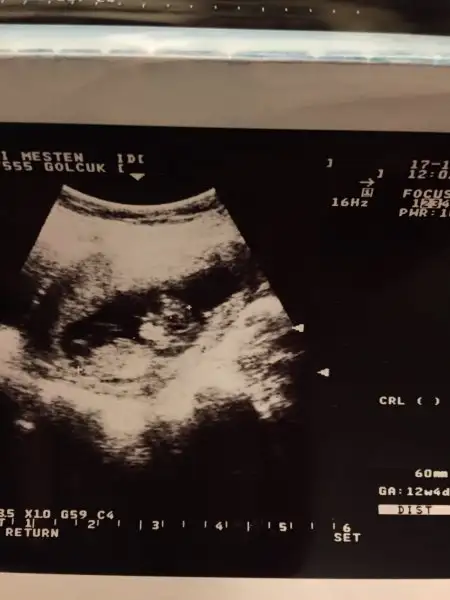

Kızlar ilk oğlumun usg lerini buldum fikir olsun diye paylaşıyorum tüm yüz hatları ağız dudak çene göz çukurları bile belli gerçekten erkek bebekler daha belirgin oluyor sanırım yinede usg cihazından olabilir bilmiyorum bu usg 9 sene öncesi